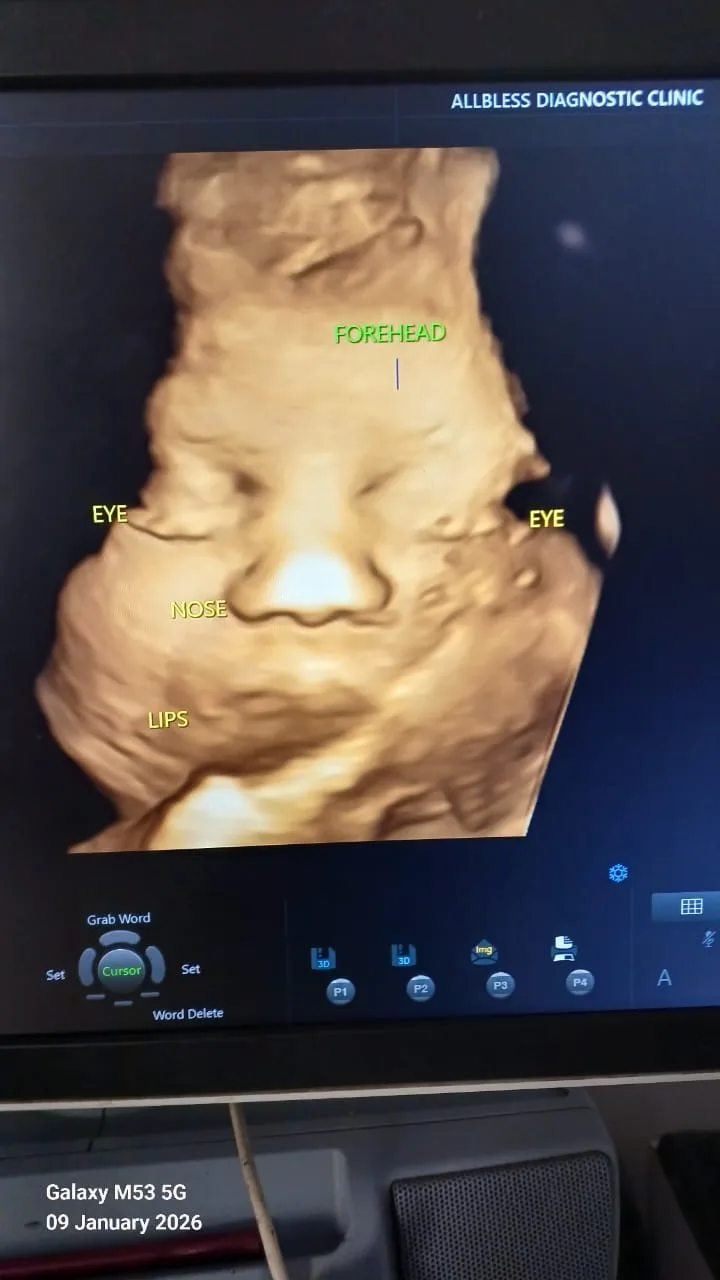

Advanced ultrasound and specialized pregnancy scans are guided by 13+ years of clinical acumen and precision.

• Early Pregnancy Scan – Confirms pregnancy location, heartbeat, and gestational age.

• NT Scan (First Trimester Scan) – Screens for certain chromosomal abnormalities.

• Anomaly Scan (18–22 weeks) – Examines the baby’s organs and structure to detect possible abnormalities.

• Growth Scan – Monitors the baby’s growth, position, and amniotic fluid levels later in pregnancy.

• Obstetric Doppler Scan – Routinely performed during pregnancy to evaluate blood flow between the mother, placenta, and baby, helping ensure the baby is receiving adequate oxygen and nutrients.

Each scan plays a crucial role in ensuring the health and development of the baby.